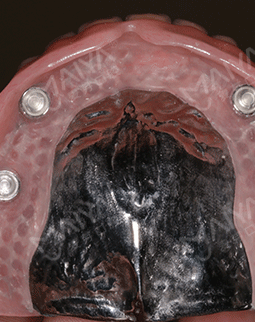

我的牙齿情况比较严重,长期缺牙,不仅缺的数目多,而且骨量出现了萎缩。虽然说麦芽的博士专家团,给我做了all-on-4种植的方案,但还需要结合骨增量来夯实地基。缺牙后提前种牙的好处,就是不会像我一样,出现严重的骨萎缩了。好在麦芽的医生种牙实力很过瘾,我现在四颗钉基本就撑起了半口牙齿,费用真的比单颗单颗种牙,节省了很多!